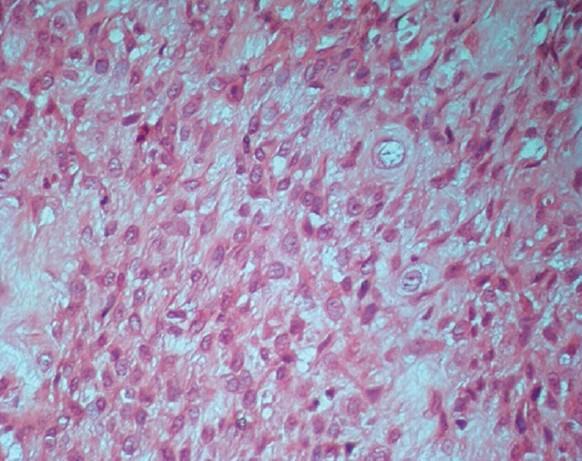

The purpose of this paper is to report a case of chondroblastic osteosarcoma in the region of the maxilla, with 5 months of evolution. The term osteosarcoma refers to a heterogeneous group of malignancies with bone formation or mesenchymal tissue with histopathological evidence of osteogenic differentiation. The pattern of chondroblastic osteosarcoma represents 25% of all reported cases of this neoplasm. Its histopathological diagnosis is based on the predominance of a chondroid matrix formed in the midst of neoplastic cells. A woman patient, 27-year old, melanoderm, presented on extraoral exam with facial asymmetry caused by the a swelling in the premaxillary region with upper lip protrusion. Intraoral exam showed a maxillary tumefaction with involvement of the vestibular and palatine regions. The computerized tomography (CT) analysis exhibited a radiolucent mass with dispersed areas of radiopacity, with poorly defined and indistinct peripheral edges. The patient was subjected to incisional biopsy and histopathological examination showed the presence of a malignant neoplasm of mesenchymal origin characterized by the presence of irregular bone trabeculae dispersed among mildly atypical chondroblastic cells. The World Health Organization (WHO) recognizes several variants that differ in location, clinical behavior and degree of cellular atypia. The conventional or classical osteosarcoma is the most frequent variant, which develops within the medullary bone. This report illustrates the rapid evolution of one of the histological variants of osteosarcoma.

本文旨在报告一例上颌骨区域的软骨母细胞性骨肉瘤病例,病程为5个月。骨肉瘤一词指的是一组异质性恶性肿瘤,具有骨形成或间充质组织,并有成骨分化的组织病理学证据。软骨母细胞性骨肉瘤模式占该肿瘤所有报告病例的25%。其组织病理学诊断基于肿瘤细胞中形成的软骨样基质占优势。一名27岁的黑皮肤女性患者,口外检查显示前上颌区域肿胀伴上唇突出,导致面部不对称。口内检查显示上颌肿物累及前庭和腭部区域。计算机断层扫描(CT)分析显示一个透射线肿物,有散在的不透射线区域,周边边缘模糊不清。患者接受了切开活检,组织病理学检查显示存在间叶源性恶性肿瘤,其特征为不规则骨小梁散在于轻度非典型软骨母细胞之间。世界卫生组织(WHO)认可几种在位置、临床行为和细胞异型程度上有所不同的变体。传统或经典骨肉瘤是最常见的变体,发生于髓腔内骨。本报告说明了骨肉瘤的一种组织学变体的快速发展情况。